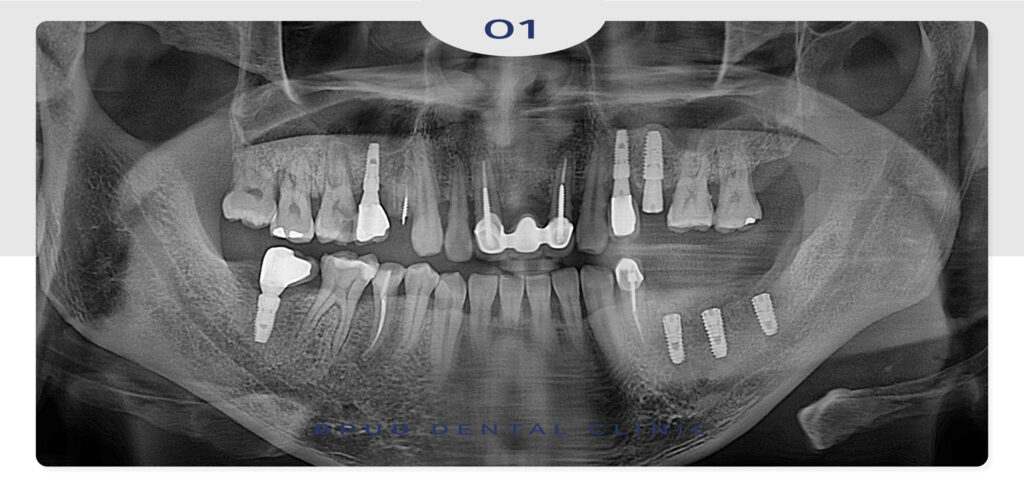

22.12.31

파노라마 촬영 시, 구강 내 전반적으로

어금니 부위에 문제가 심하게 진행되었고

기존 임플란트도 제거하고 재수복이 필요한

상황이었습니다.